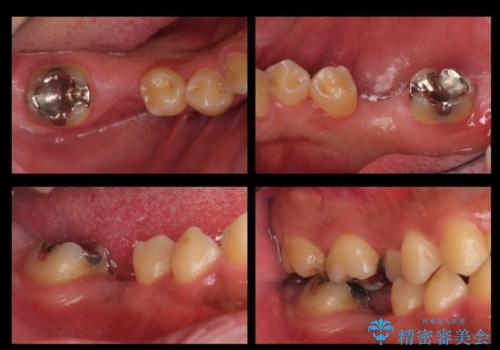

- 右下の奥歯にインプラントを入れたいと来院。

抜歯から時間が経っており、骨が十分あったためすぐにインプラントを入れることが可能でした。骨も補う必要がありませんでした。

インプラント手術時に同時に親知らずの抜歯も行い、腫れや痛みなどを1度で終わらせるようにしました。